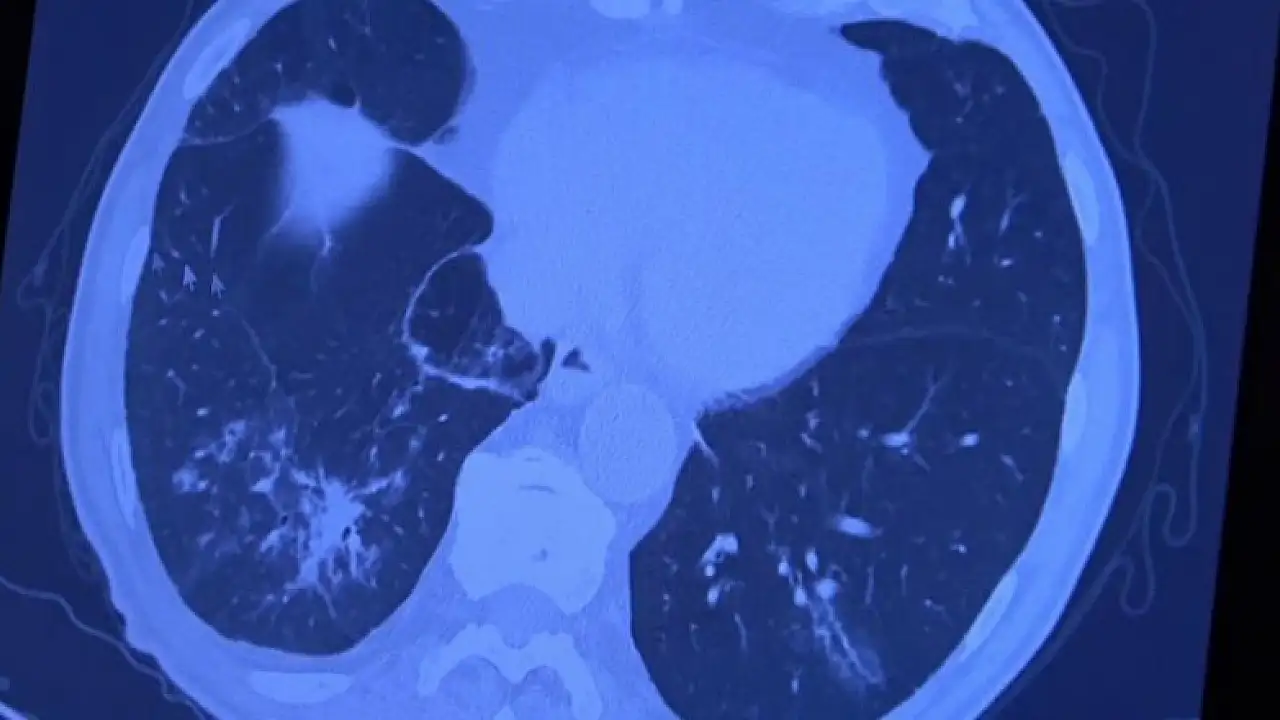

Korona virüs hastalığı genç nüfusta daha fazla görülmeye başlarken Covid-19 aşıları tamamlanan 60 yaş üstü vatandaşlardan bazıları ise korona virüse yakalanmaya devam ediyor. VM Medical Park Samsun Hastanesinde görev yapan Göğüs Hastalıkları Uzmanı Prof. Dr. Şevket Özkaya ise aşının gerçek yaşam sonuçlarını gözler önüne serdi. 2. doz aşıları tamamlanmış fakat Covid-19 servisinde yatan hastaların akciğer tomografilerini inceleyen Prof. Dr. Özkaya, bu kişilerin akciğer tutulumları olduğu halde hastalığı hafif atlattıklarını söyledi.

Bugüne kadar aşının etkilerini hep laboratuvar ortamında antikor üretip üretmemesi ile değerlendirdiklerini belirten Prof. Dr. Özkaya, "Vatandaşlarımız aşılarını olduktan sonra ilk gerçek yaşam sonuçlarını yeni yeni almaya başladık. Gerçekten aşı yaptığımızda antikor oluşturuyor ama bu antikor kişiyi koruyacak mı diye merakla beklediğimiz sorunun cevabını, insanlar 2. doz aşısını olduktan bir ay sonra ortaya çıkmaya başladı. Bu hastalar korona virüsü kaptığında yeni yeni korumaya başladığını anladık. Bir örnek vermem gerekirse, 84 yaşında bir hastamız 2. doz aşısını olduktan sonra eşiyle beraber Covid-19 oluyor. Korona virüsü akciğer tutulumları olduğu halde çok hafif şekilde atlattılar. 65 yaşında başka bir hastamızı göstermek gerekirse, bu hastamız da 2. doz aşısını olmuş ve aradan 1 ay geçtikten sonra antikor da oluşmuş. Bu antikor bu kişiyi koruyacak mı diye gerçek yaşam sonuçlarına baktığımızda, koronanın hastanın akciğerlerine indiği halde çok hafif atlattığını görüyoruz. Eğer bu kişi aşı olmasaydı, hastaneye yatarak daha ağır geçirebilirdi" diye konuştu.

Covid-19 servisinde yatan hastaların yüzde 80'inin gençlerden oluştuğunun altını çizen Prof. Dr. Özkaya, "Artık daha genç hastaların mutant virüsle karşılaştıkları için daha ağır geçirdiği görüyoruz. 60 ve 65 yaş üstünü ise aşıyla sigortaladığımızı düşünüyoruz. Aşının gerçek yaşam sonuçlarının olumlu olduğunu görüyoruz. Aşı olanlar virüse yakalandıkları halde çok hafif veya hastaneye yatmadan atlatıyorlar. Şu an servisimizde yatan hastaların yüzde 80'inini genç hastalar oluşturuyor. Artık 60 yaş üstünde çok fazla hasta görmüyoruz. Örneğin (akciğer filmini gördüğümüz) 40 yaşındaki bir hastamız aşılanmadığı için mutant virüse yakalanmış. Akciğerleri çok kötü durumda ve hastanede yatıyor. 24 yaşında bir genç kızımızda ise ciddi akciğer tutulumları görüyoruz. 49 yaşında bir hastamızı ise maalesef çok ciddi akciğer tutulumu ve neredeyse paramparça bir akciğerle yoğun bakımda takip ediyoruz" şeklinde konuştu.